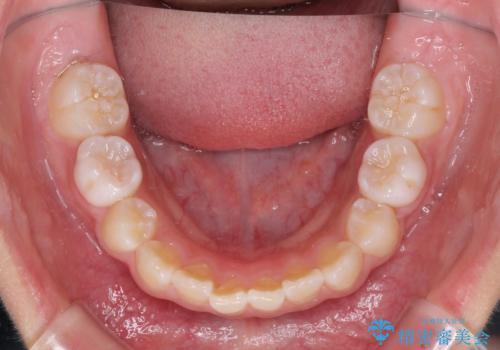

左上の犬歯が低位に埋伏しており、将来八重歯になるリスクが高いと判断されたため、補助装置とワイヤーを用いて犬歯を通常の位置まで移動させることとしました。

今後残っている乳歯が抜け、永久歯が萌出してくるため、調整可能なリンガルアーチを用いて保定を行っています。

12歳臼歯が萌出するまで経過観察を行い、すべての歯が萌出した後に、全顎矯正治療(Ⅱ期治療)を行っていきます。